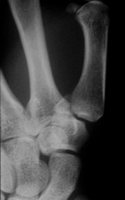

Der Sturz auf den gestreckten Daumen ist meist die

Ursache für diese Problemfraktur. Der Zug der Sehen verursacht

die Dislokation. Die geschlossene Reposition und Gipsfixation kann

die Frakturstellung nicht aufrechterhalten. Die Stabilisierung mit

Kirschnerdrähten, Schrauben oder am einfachsten mit dem Minifixateur

sind die Verfahren der Wahl.